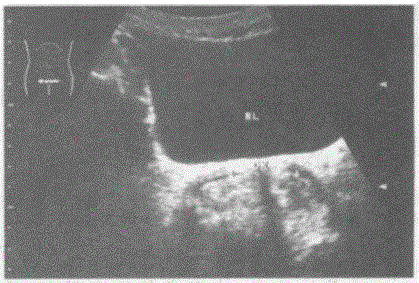

临床资料:女性,24岁,常规体检。超声综合描述:横切面子宫底部平滑,横径增宽,内可见两个宫腔内膜回声,中央有条样分隔,两部分内膜均延续至宫颈。...

问题 临床资料:女性,24岁,常规体检。 超声综合描述:横切面子宫底部平滑,横径增宽,内可见两个宫腔内膜回声,中央有条样分隔,两部分内膜均延续至宫颈。 超声提示:

选项 A.双角子宫 B.不完全性纵隔子宫 C.完全性纵隔子宫 D.鞍状子宫

答案 C